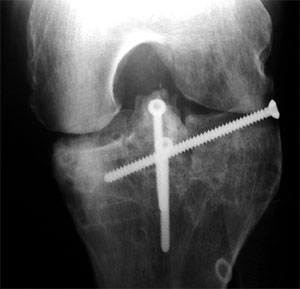

Und so sieht das ganze radiologisch aus (links die Bilder vom Juli 2001 mit den 5 alten Schrauben, rechts die Bilder vom Mai 2002 mit den 3 neuen Schrauben - auf die Bildfragmente klicken, um eine grössere Fassung des Ausschnittes zu sehen).

Hier klicken für grössere Fassung dieses BildteilsHier klicken für grössere Fassung dieses BildteilsHier klicken für grössere Fassung dieses BildteilsHier klicken für grössere Fassung dieses Bildteils

1. Das Problem, Bild links oben: Die zu hoch eingewachsene Eminenz (im Kniegelenk höchster Teil des Schienbeins, blau eingefärbt) verhindert die Streckung, weil sie am Oberschenkel anstösst, wenn das Bein gestreckt werden sollte (1).

2. Die Lösung: Weil an der Eminenz Bänder angewachsen sind, kann man das zu hoch stehende Fragment nicht einfach abhobeln - man muss es nach unten ziehen (2). Dafür muss aber zuerst Platz geschaffen werden...

3. Die Ausführung: Am Schienbein werden diverse Schnitte vollzogen. Im Bild rechts oben (3) ist der Schnitt von vorne sichtbar, im rechten unteren Bild (4) ein Schnitt von oben. Aus dem Schienbein ein Keil entfernt, sodass die zuerst von überschüssigen Knochenfragmenten befreite Eminenz gewissermassen nach vorne und unten ins Schienbein geklappt werden und mit drei Schrauben festgemacht (5) werden kann. In den unteren beiden Bildern ist auch schön sichtbar, dass die Eminenz nun wieder eine normalere Form hat.

Schön sichtbar sind auch die alten Löcher der im November 2001 entfernten Schrauben sowie in den Bildern rechts (gelbe Pfeile) eine alte Unterlagsscheibe, die während dem Sommer 2001 im Knochen festgewachsen war und im November nicht herausgefischt werden konnte (auf die Bildfragmente klicken, um eine grössere Fassung des Ausschnittes zu sehen).

Die neue Konstruktion von vorne bei ca. 45° gebeugtem Knie. Rechts von der Eminenz ist einer der frischen Schnitte im Knochen sichtbar.